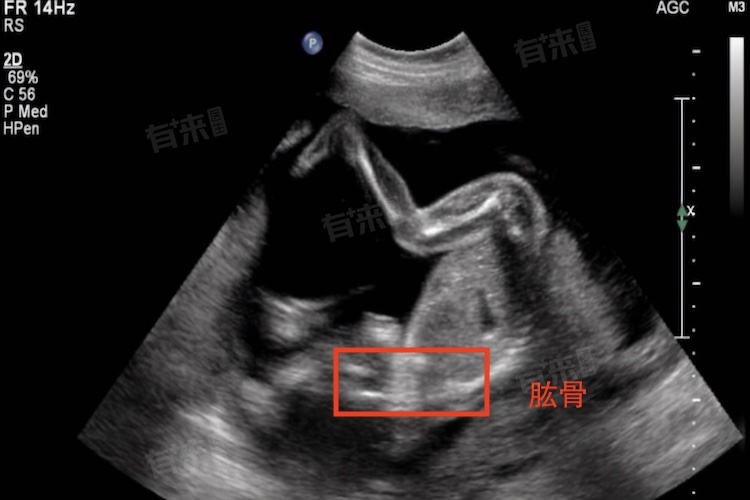

1、定期超声波检查:通过定期进行超声波检查,医生可以准确测量胎儿的肱骨长度。通常在孕中期(20周左右)和晚期进行多次检查。

2、选择合适的测量时间:肱骨长度在孕中期和晚期增长较快,选择合适的测量时间可以更准确地评估胎儿的发育情况。

3、专业医生操作:超声波检查应由经验丰富的医生或技术人员操作,以确保测量结果的准确性。

4、记录和对比数据:每次检查后,记录肱骨长度的数据,并与标准生长曲线进行对比,评估胎儿的生长是否在正常范围内。

5、综合评估:肱骨长度应与其他生长指标(如双顶径、腹围等)综合评估,以全面了解胎儿的发育情况。